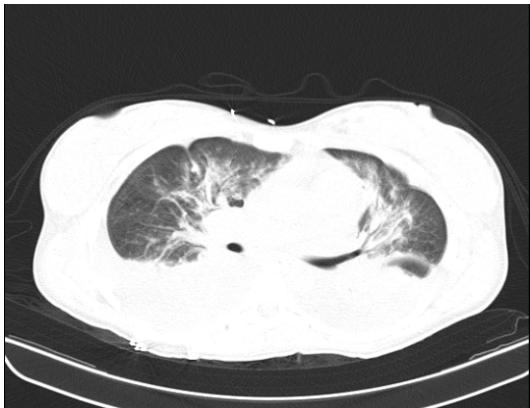

On day 4 of intravenous antibiotic therapy with ertapenem (twelfth day of hospitalization, seventh day in the unit) the patient suddenly became tachypneic with saturations of $88\%$, for which a chest tomography was indicated (figure 2 and figure 3) where It showed a large left pleural effusion, which is why a thoracentesis was indicated, draining $620~\mathrm{cc}$ of clear liquid without infectious characteristics in the bacterial culture cytology reading and a negative fungal test. Patient with immediate improvement after drainage of the pleural effusion; for which she was transferred to a general gynecological hospitalization receiving antibiotic treatment with stable vital signs, afebrile, without loss of fetal well-being evaluated by obstetric ultrasound, who completed antibiotic treatment and proposed adjuvant immunotherapy scheme with immunoglobulin G enriched with IgM and IgA with adequate drug tolerance and favorable clinical course.

Figure 2: Chest tomography, coronal section. Bilateral pleural effusion. Source: authors. Figure 3: Chest tomography, axial slice. Bilateral pleural effusion. Source: authors.